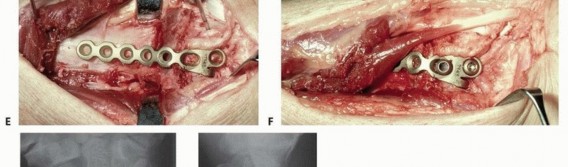

### TECH FIG 3 • A. Corticocancellous bone graft is harvested from the iliac crest. B. After final sculpting, it is applied to the osteotomy site. C. Autogenous cancellous bone graft is harvested from the iliac crest using a trephine. D. A 2.0-mm condylar blade plate can provide fixed-angle internal fixation. E,F. Intraoperative photographs of the fixation. G,H. Final anteroposterior (AP) and lateral radiographs. (Copyright Diego Fernandez, MD, PhD.) When a structural, corticocancellous bone graft is used, a single plate or a plate and separate screw may be adequate ( TECH FIG 3D-H). Plates with angular stable screws or blades in the distal fragment may be more reliable than standard screws, particularly if the bone is of poor quality and if nonstructural graft is chosen. Once implants are placed and stability is ensured, remove all provisional fixation devices. This entire process is monitored using image intensification to confirm appropriate osteotomy site, correction of alignment, and implant placement. Repair the extensor retinaculum with absorbable suture. In some cases, a flap of retinaculum is brought deep to the tendons to add a layer of protection between the implants and extensor tendons. We usually do not close the retinaculum, and we no longer make retinacular flaps. The tourniquet is deflated and hemostasis ensured. The skin is closed. A bulky dressing incorporating a volar plaster wrist splint is applied. 1. ## Volar Extra-articular Distal Radius Osteotomy ### Exposure 148 Use a volar-radial Henry (flexor carpi radialis [FCR]) approach for both dorsally and volarly angulated malunions (see FIG 2C,D). Make a 5- to 7-cm longitudinal incision over the FCR tendon ending at the wrist flexion crease. If more exposure is required, the incision is angled or zigzagged at least 45 degrees toward the scaphoid distal pole. Incise the FCR sheath, retract the tendon ulnarly, and incise the floor. Leave the radial artery undissected and protected in the radial soft tissues. Sweep the fat overlying the pronator quadratus together with the digital flexors and median nerve ulnarward with a sponge or blunt elevator. Proximally in the incision, elevate the most distal aspect of the origin of the flexor pollicis longus from the volar distal radius (taking care to cauterize a consistent artery in this region) and retract it ulnarly with a small Hohmann retractor placed around the ulnar border of the radius. Expose the radial border of the radius using a blunt elevator and Hohmann retractors. Incise the pronator quadratus over its most radial and distal limits (L-shaped incision) and elevate it subperiosteally. Leaving the periosteum with the muscle can facilitate later repair. For dorsally angulated malunions, release of the radial and dorsal soft tissues facilitates realignment. The brachioradialis is Z-lengthened and the periosteum is elevated from the radius shaft proximally.

TECH FIG 4 • A-D. Realignment and provisional fixation of an extra-articular dorsally displaced malunion in the patient in FIG 2C,D. After osteotomy in the manner detailed earlier (for the dorsal approach to malunions), pronate the proximal radius shaft out of the wound, providing access to the dorsal periosteum, which can be isolated and divided. With the release of the brachioradialis and the dorsal periosteum, realignment of the radius is usually comparable to an acute fracture. Volarly angulated malunions do not need an extensive soft tissue release in most cases. The plate can facilitate realignment by pushing the distal fragments into position as the proximal screws are tightened. ### Realignment and Provisional Fixation The fragments are realigned using the techniques described earlier ( TECH FIG 4). The techniques are similar to those for acute fractures once an adequate soft tissue release has been performed. Apply a fixed-angle volar implant. Insert provisional Kirschner wires either through or adjacent to the plate (see TECH FIG 4). ### Plate Fixation Placement of the plate will frequently help reduce the proximal and distal fragments ( TECH FIG 5A,B). After final plate fixation and removal of provisional fixation, apply cancellous graft to the osteotomy site ( TECH FIG 5C-F). Excellent access is available radially for placement of the bone graft. The tourniquet is deflated and hemostasis ensured. Repair the pronator quadratus if possible. It can be sutured to the brachioradialis tendon. The skin is closed. A bulky dressing incorporating a volar plaster wrist splint is applied. 149

### TECH FIG 5 • A. Fluoroscopic image of plate fixation and realignment. B. Defect after correction. Autogenous cancellous graft (C) and graft placement (D), showing final clinical appearance. E,F. Final PA and lateral radiographs. (Copyright Diego Fernandez, MD, PhD.) -